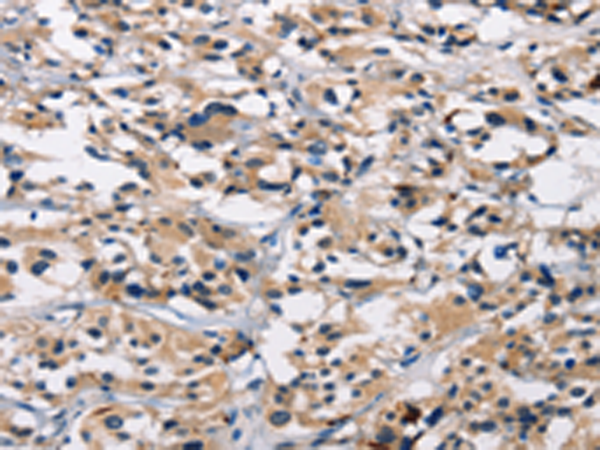

分类: 科研抗体货号: P04769别名: CD318; TRASK; SIMA135应用: WB,IHC反应种属: Human